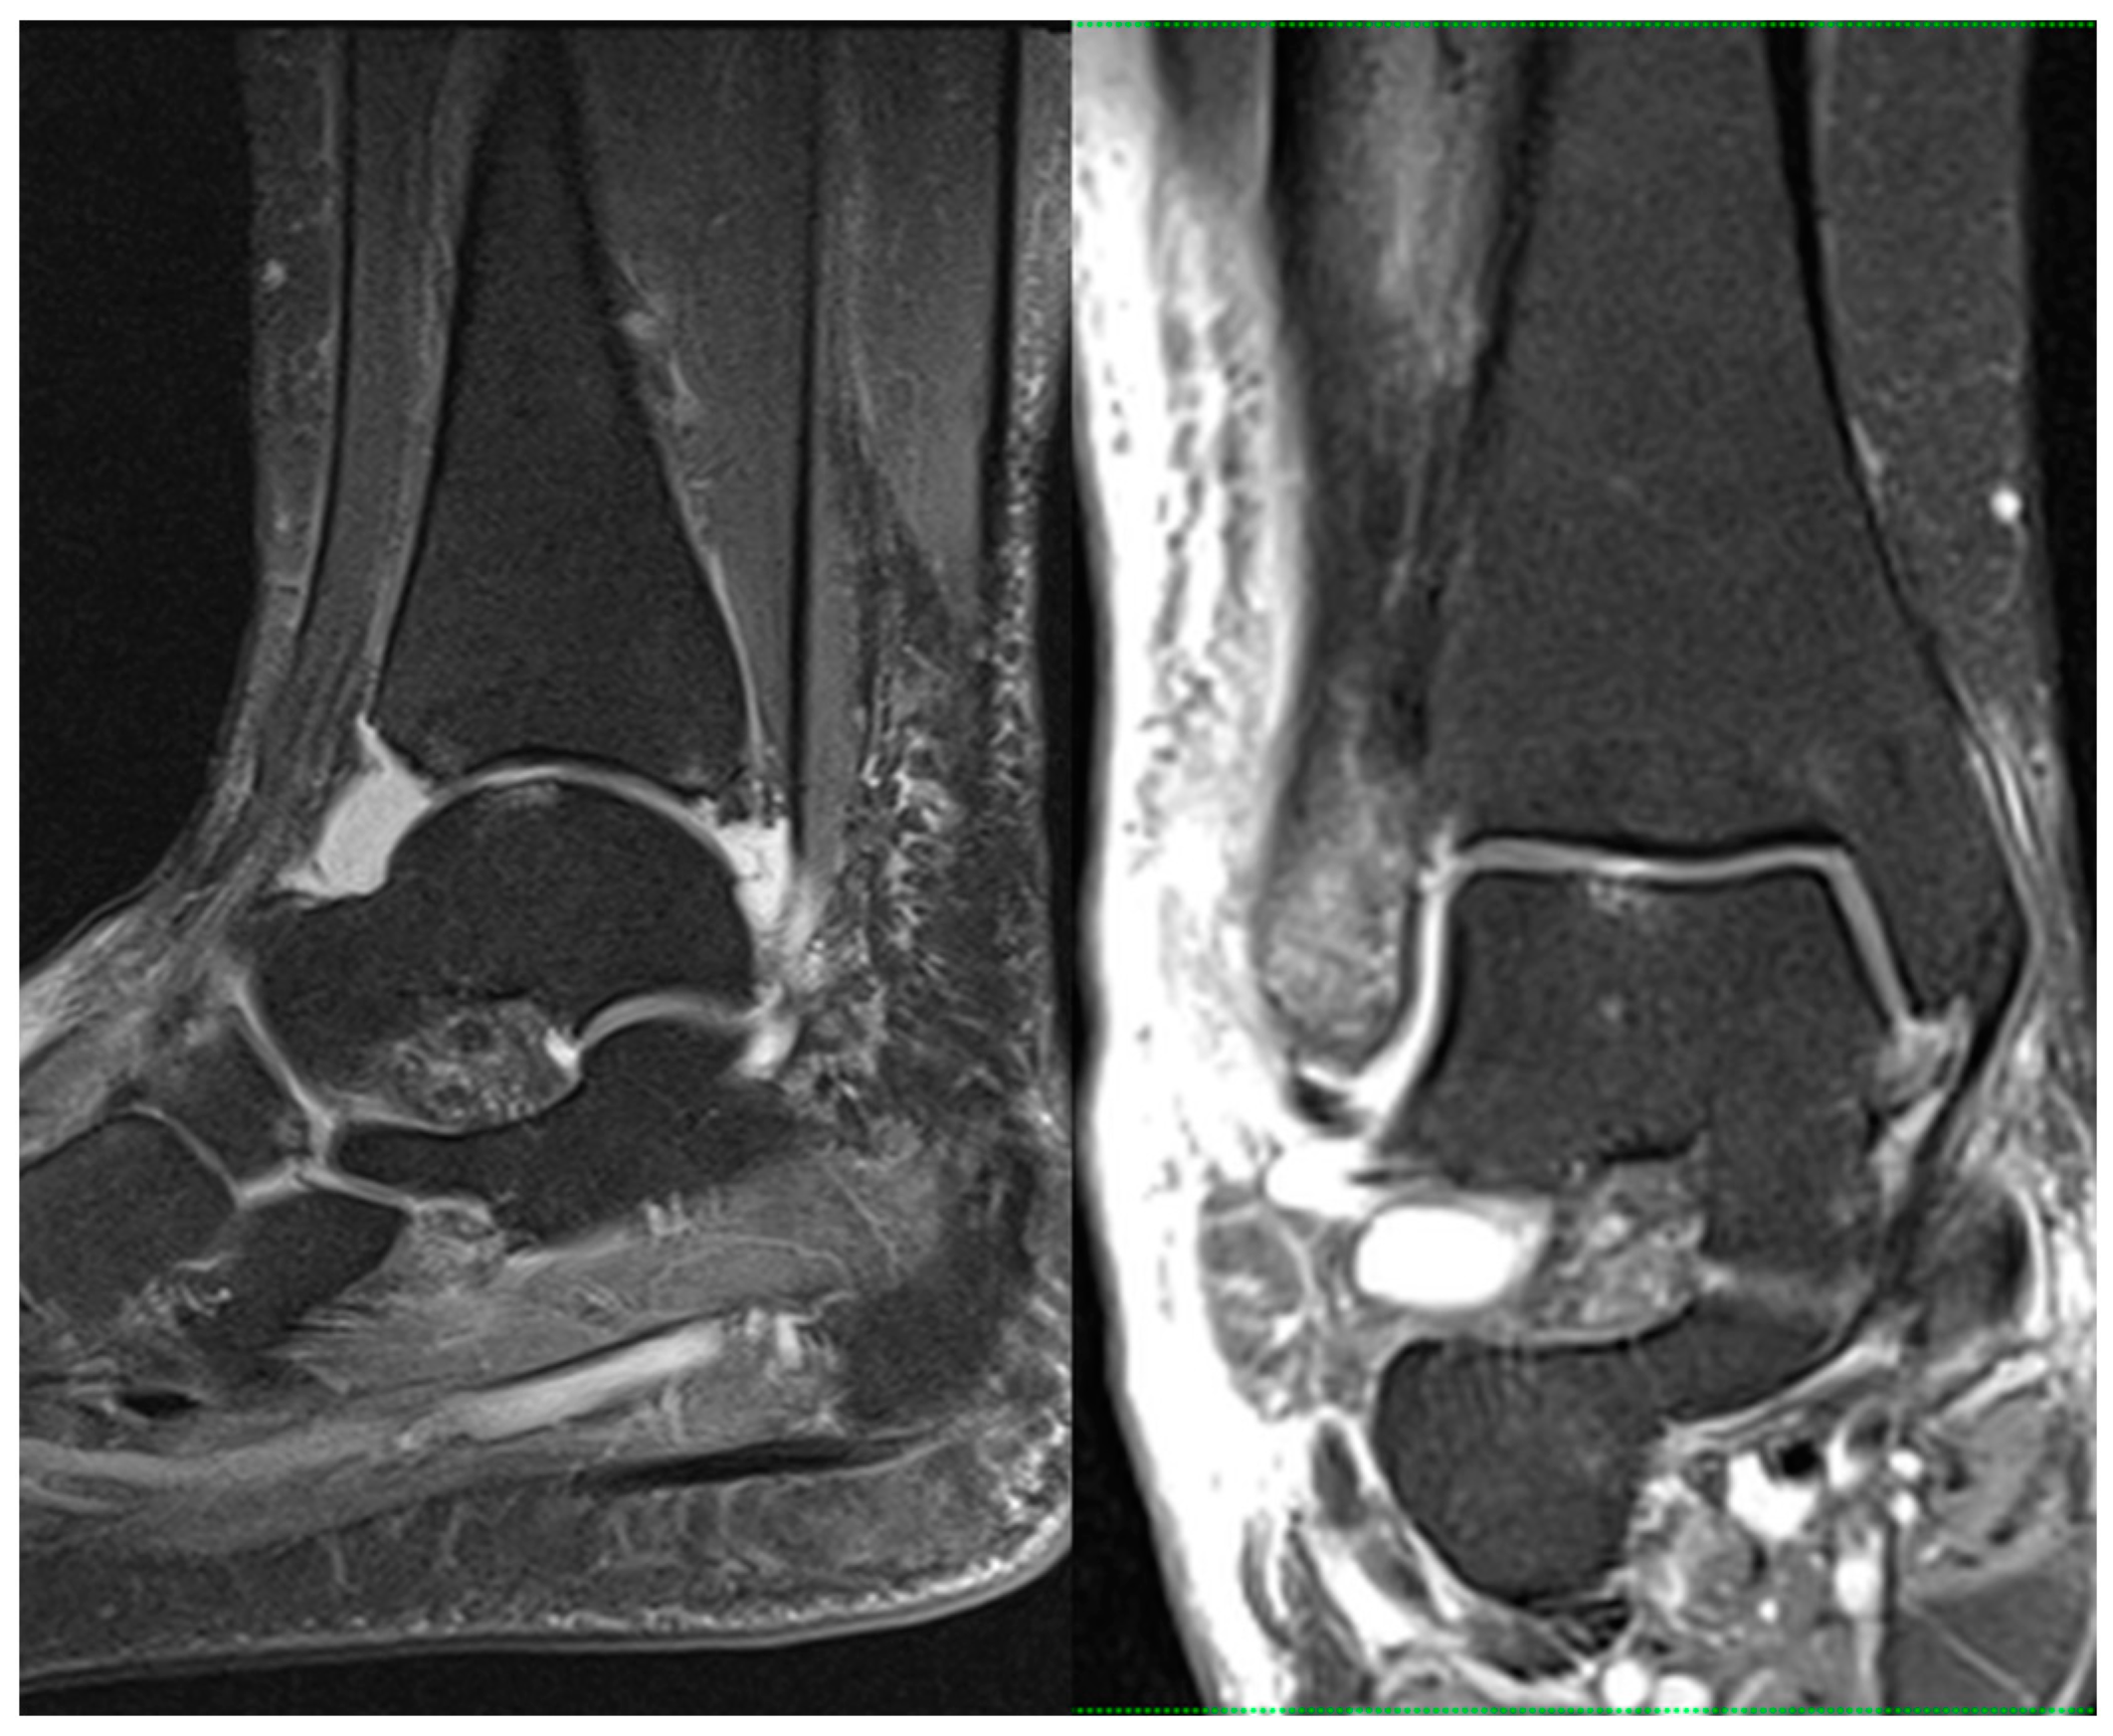

Preoperative MRIs were obtained for all included patients using a standard protocol to assess cartilage involvement including prevalence, grade, and location. All MRI scans were performed within 10 days of trauma. All scans were performed within our institution using a 1.5 T MRI scanner (Magnetom Sola, Siemens Healthineers, Germany). Standard pulse sequences included three-plane proton-density (PD) and sagittal short tau inversion recovery (STIR) sequences (Figure 1).

Figure 1.

Sagittal (left) and coronal (right) proton-density-weighted turbo spin echo fat saturation MRI sequences (PD tse fs) showing CL of the talar dome in a 52-year-old female with an acute ankle fracture.